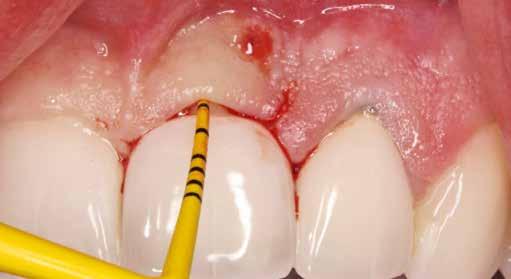

1. ábra: A műtét előtti szituáció, megfigyelhető az implantátumok közötti konkáv terület, ahova könnyen beragad az ételmaradék, és könnyen kialakul a periimplantitis.

Esetleírás

Egy 47 éves páciens jelentkezett nálunk egy alsó, hátsó foghiánnyal, ahol jelentős csontfelszívódást tapasztaltunk a moláris fogak korábbi eltávolítása miatt (1. ábra). Két implantátum körül is volt ínyrecesszió, illetve a keratinizált íny mennyisége minimális volt (kevesebb, mint 1 mm). 4 hónappal az implantációt követően ínykorrekciót végeztünk.